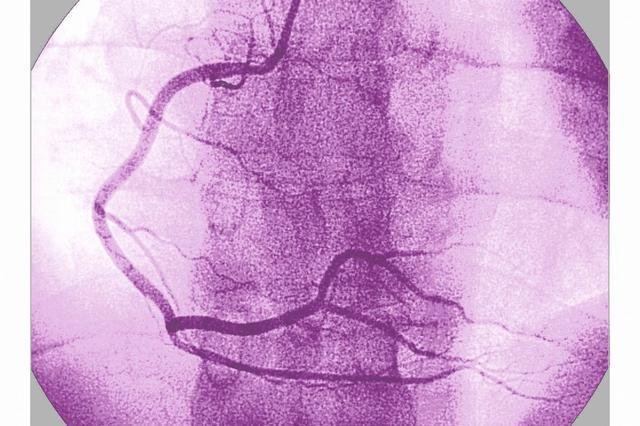

为心脏供血的是冠状动脉。冠脉造影可以清晰显示冠状动脉及其分支的走向、形态及有无狭窄,狭窄的部位、程度、范围,以及侧支循环,并可据此指导进一步治疗;评价冠状动脉功能性的改变(冠状动脉的痉挛);同时也可以进行左心室造影,从而对心功能进行评价。

冠脉造影现已广泛应用于临床,被认为是诊断冠心病的“金标准”,它是一种较为安全可靠的有创诊断技术。

张先生,男,45岁,公司高管,来我院健康体检,身高175厘米,体重98千克,血压145/88毫米泵柱,饮食偏成,有25年饮酒史,有23年烟龄,很少参加体育运动,父亲因冠心病去世,母亲健在,患高血压病。近1月来无明显诱因下反复出现心悸、胸闷等不适,心电图检查未见明显异常,建议行冠脉造影检查,结果显示左前降支狭窄达90%,心内科专家及时予以支架植入,避免了急性心肌梗死的发生。